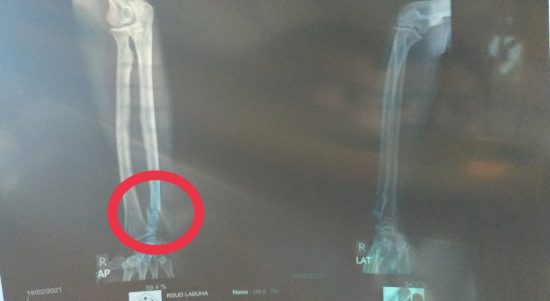

HALSEL, CN – Seorang warga di Desa Sum Kecamatan Obi Timur Kabupaten Halmahera Selatan (Halsel) Maluku Utara bernasib naas. Dia dianiaya hingga mengalami patah tulang di tangan kanan. Rusuk dan tangan kiri bengkak. Hal tersebut dibuktikan melalui hasil Rongten, Jumat (19/2/2021).

Saat itu, korban menjalani perawatan medis di Puskesmas Desa Sum. Setelah itu, dirujuk ke Rumah Sakit Umum Obi. Setalahnya lagi, kembali dirujuk ke RSUD Labuha untuk mengetahui hasil Rongten.